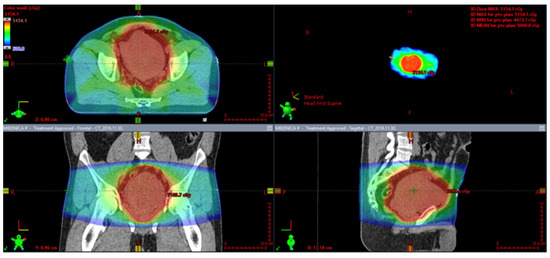

7.2. Perioperative Radiotherapy

7.4. Definitive Radiotherapy

- Krengli, M.; Cena, T.; Zilli, T.; Jereczek-Fossa, B.A.; De Bari, B.; Villa Freixa, S.; Kaanders, J.; Torrente, S.; Pasquier, D.; Sole, C.V.; et al. Radiotherapy in the treatment of extracranial hemangiopericytoma/solitary fibrous tumor: Study from the Rare Cancer Network. Radiother. Oncol. 2020, 144, 114–120. [Google Scholar] [CrossRef]

- Haas, R.L.; Walraven, I.; Lecointe-Artzner, E.; Scholten, A.N.; van Houdt, W.J.; Griffin, A.M.; Ferguson, P.C.; Miah, A.B.; Zaidi, S.; DeLaney, T.F.; et al. Radiation Therapy as Sole Management for Solitary Fibrous Tumors (SFT): A Retrospective Study From the Global SFT Initiative in Collaboration With the Sarcoma Patients EuroNet. Int. J. Radiat. Oncol. Biol. Phys. 2018, 101, 1226–1233. [Google Scholar] [CrossRef]

- Spałek, M.J.; Teterycz, P.; Borkowska, A.; Poleszczuk, J.; Rutkowski, P. Stereotactic radiotherapy for soft tissue and bone sarcomas: Real-world evidence. Ther. Adv. Med. Oncol. 2022, 14, 17588359211070646. [Google Scholar] [CrossRef] [PubMed]